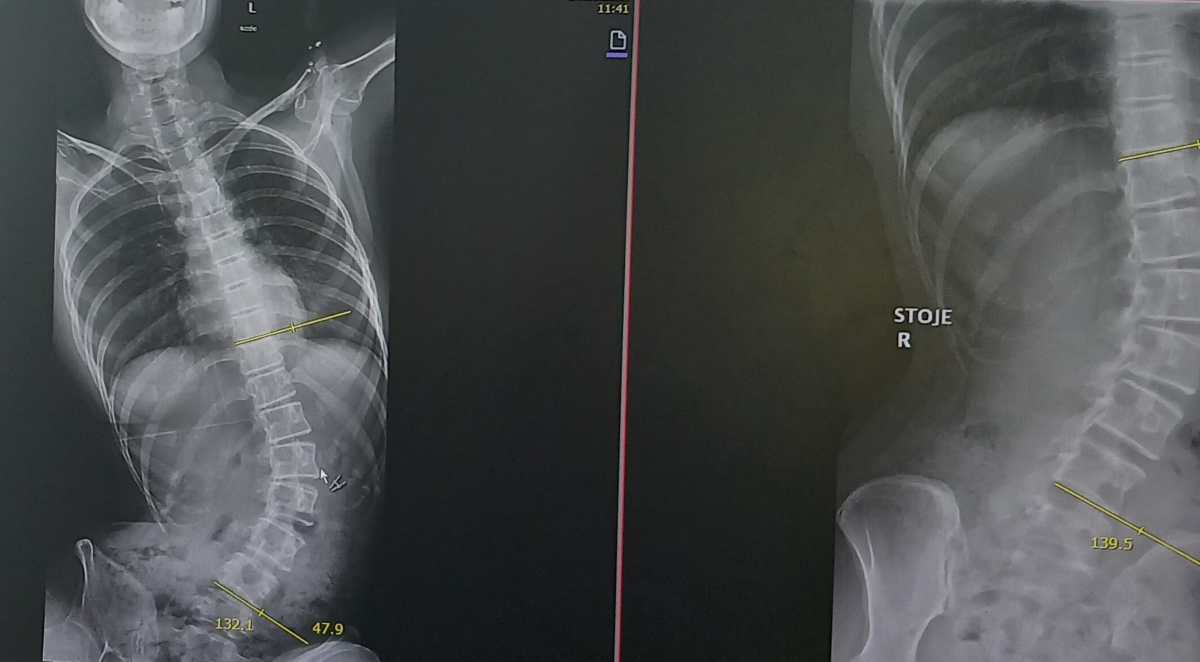

Aida in njena družina se z Aidino boleznijo spopadajo od njenih ranih let. Aida ima močne epileptične napade, pridružila pa se je še z močno osteoporozo, ki ji krivi hrbtenico in povzroča močne bolečine. Dekle je močno prizadeto, mama pravi, da je na ravni šestmesečnega otroka. Zanjo že vsa leta lepo skrbijo, prilagajajo svoje življenje in ji omogočajo čim več, kar lahko.

Sedaj pa so se znašli pred veliko prepreko. Aidi se zdravstveno stanje močno slabša, najbolj učinkovito ji lahko pomaga operacija z lastnimi matičnimi celicami, ki jo v Evropi opravljajo le v Turčiji. Starša Ermina in Edis sta se znašla pred velikim izzivom, saj morata za dve operaciji zbrati 30.000 evrov. Nekaj sta (tudi s pomočjo dobrih ljudi) že zbrala, vendar jima še precej manjka.